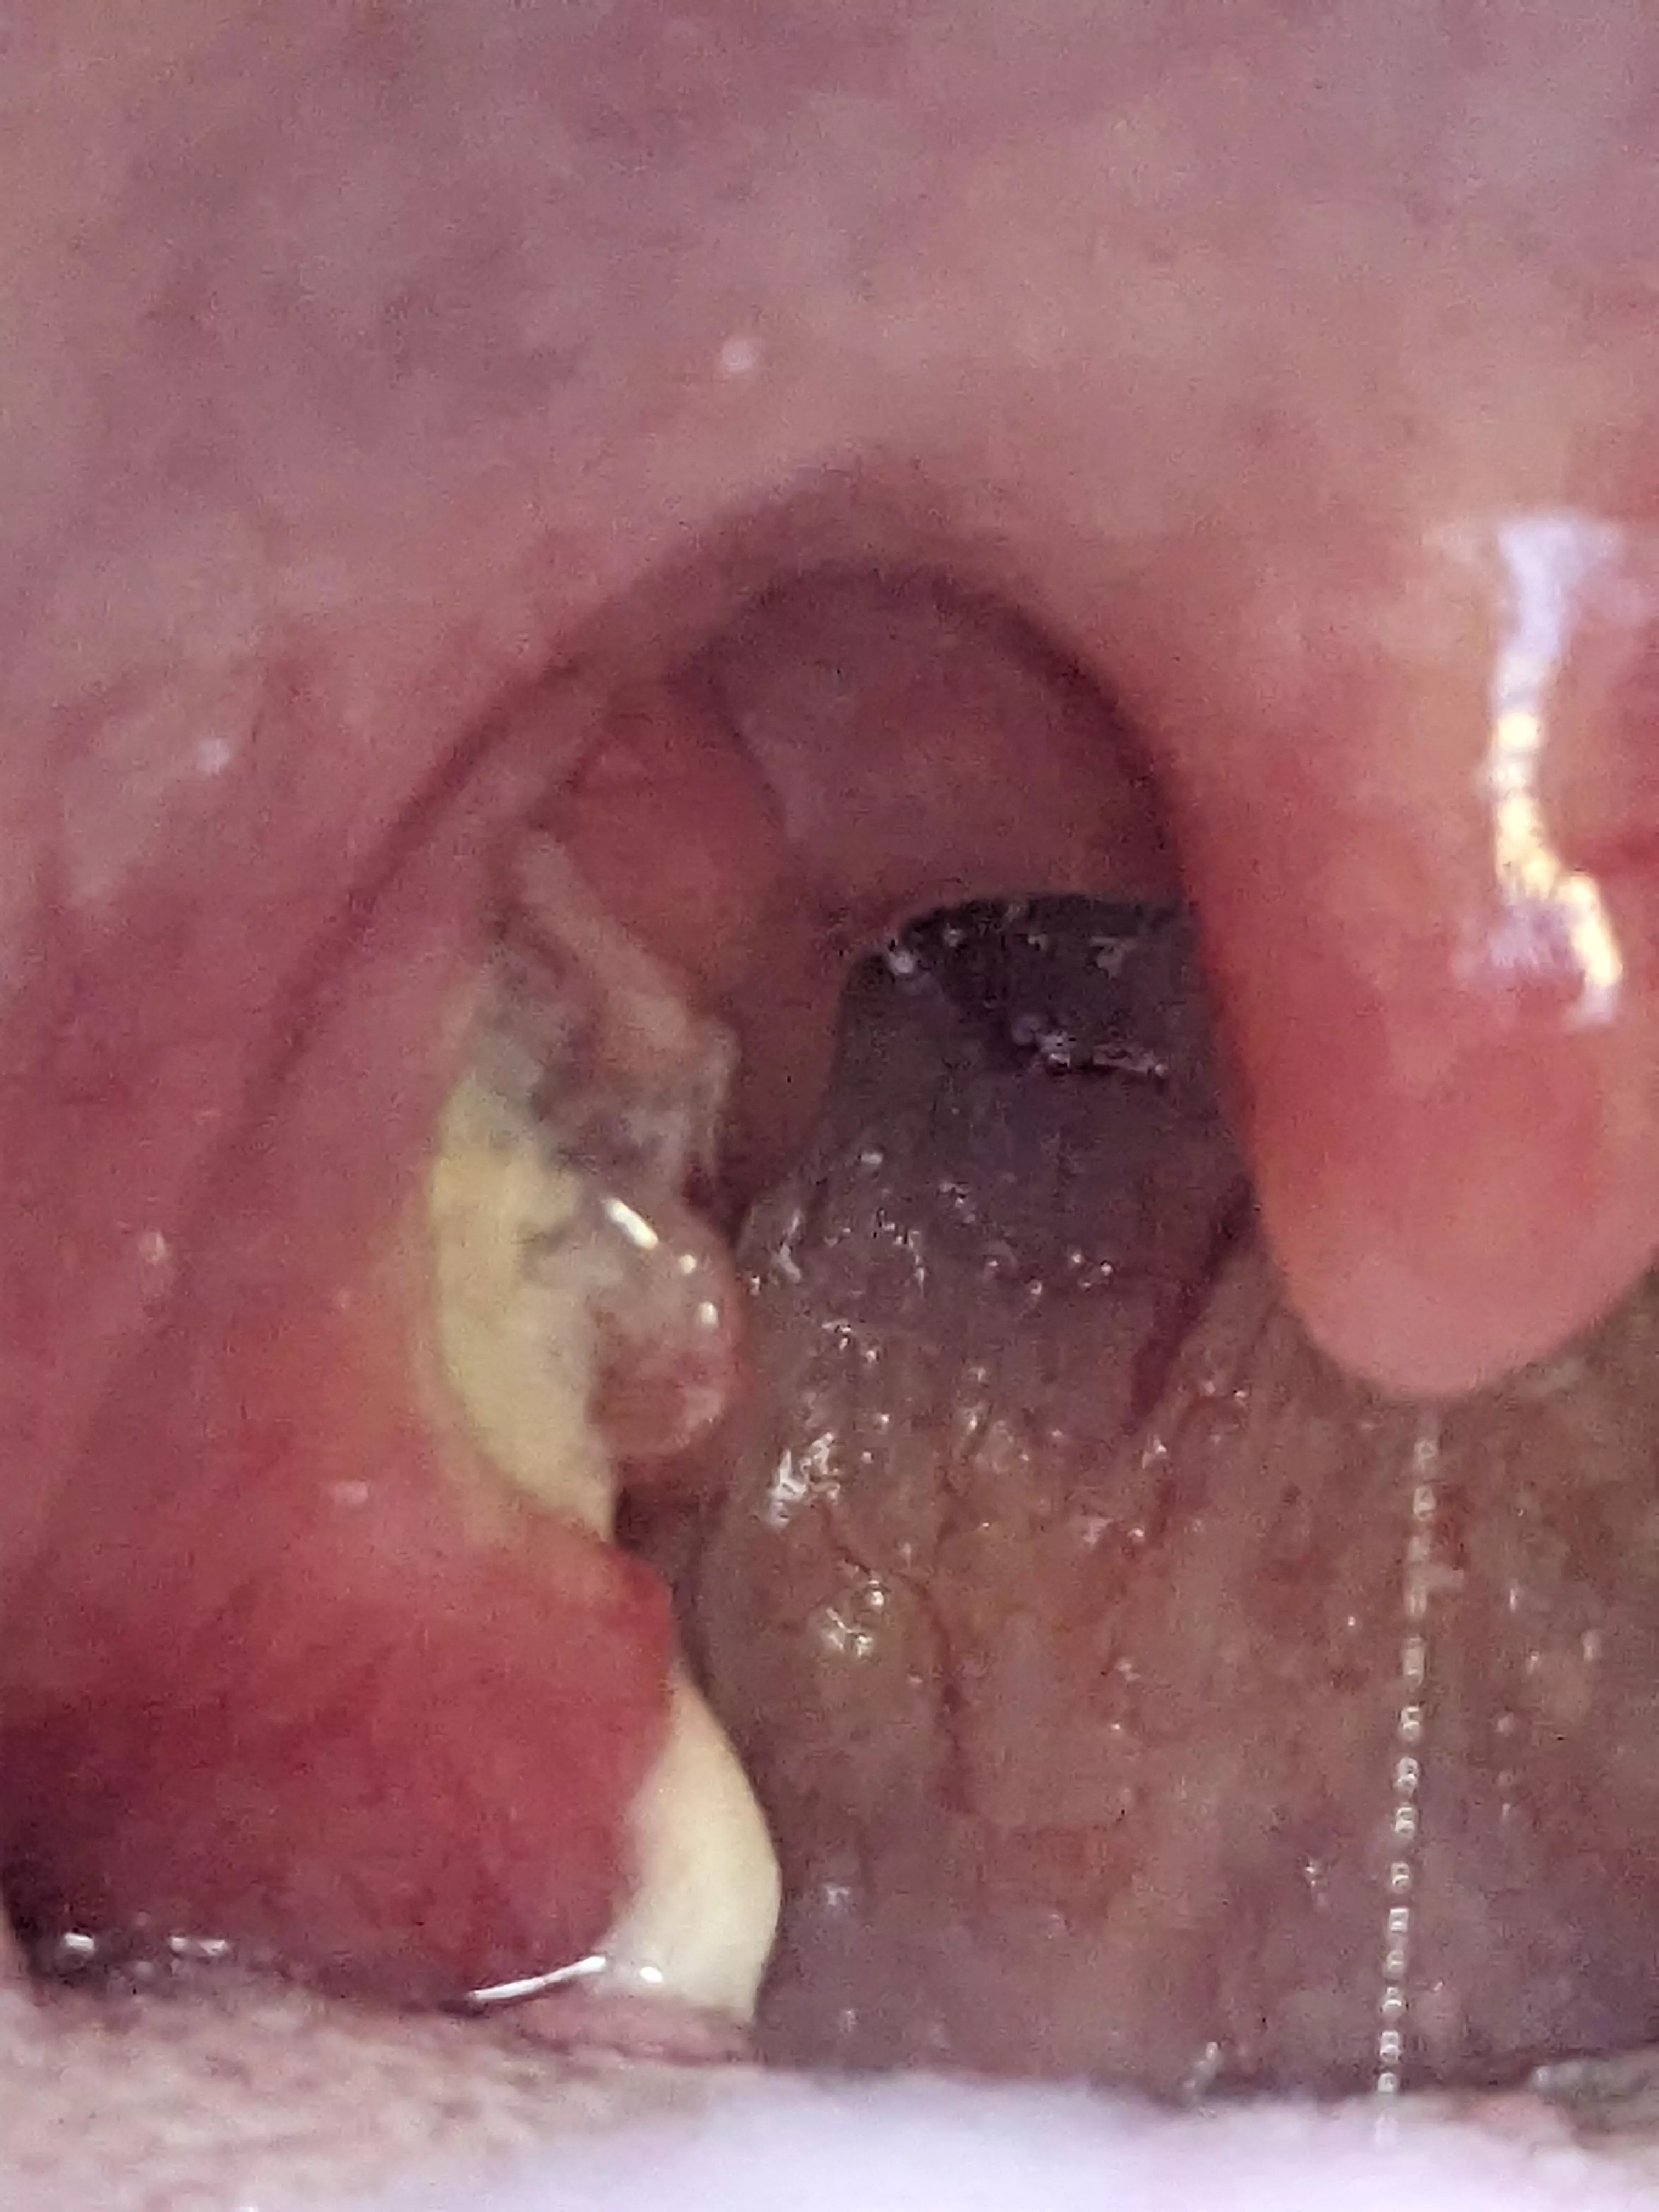

The day after suspected Quincy... nudes

Category: popping

Potential paronychia